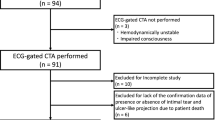

Distensibility measurements of the aorta were performed in 67 patients with AAA. Time-resolved images were acquired with a four detector-row CT system using a modified CT-angiography protocol. Pulsatility-related cross-sectional area changes were calculated above and at AAA level by semiautomatic segmentation; distensibility values were obtained using additional systemic blood pressure measurements. Values were compared for small Ø< 5 cm (n=44) and large Ø> 5 cm (n = 23) aneurysms.

Sixty-seven consecutive patients with known infrarenal abdominal aortic aneurysm who had presented to the Department of Vascular Surgery were studied. The decision to subsequently operate or not upon a patient in this study was entirely at the discretion of the surgeons in charge. Approval of the local ethics committee and informed consent were obtained properly. Twenty-three patients presented an aneurysm diameter of less than 5 cm (mean, 3.9; ±0.9 cm); 44 presented with aneurysms of more than 5-cm diameter (mean 5.6; ±0.6 cm). The clinical characteristics of the population collected for this study are listed in Table 1. Mean age for the patients with larger sized aneurysms was 67±9 years including 35 men and 9 women. Mean age for the patients with smaller sized aneurysms was 69±9 years including 21 men and 2 women. Mean heart rate during examination was 67±12 bpm; no medication was used to reduce the heart rate during the examination.